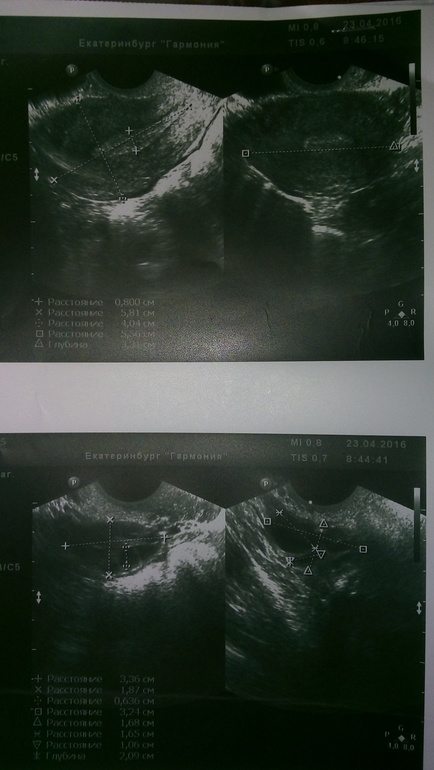

ВЫ не полностью обследованы. Сдавайте АМГ, определяйте ГСПГ, надо высчитать индекс андрогенов. Исследуйте кровь на глюкозу и инсулин. Я бы также хотела бы взглянуть на Ваши УЗИ.